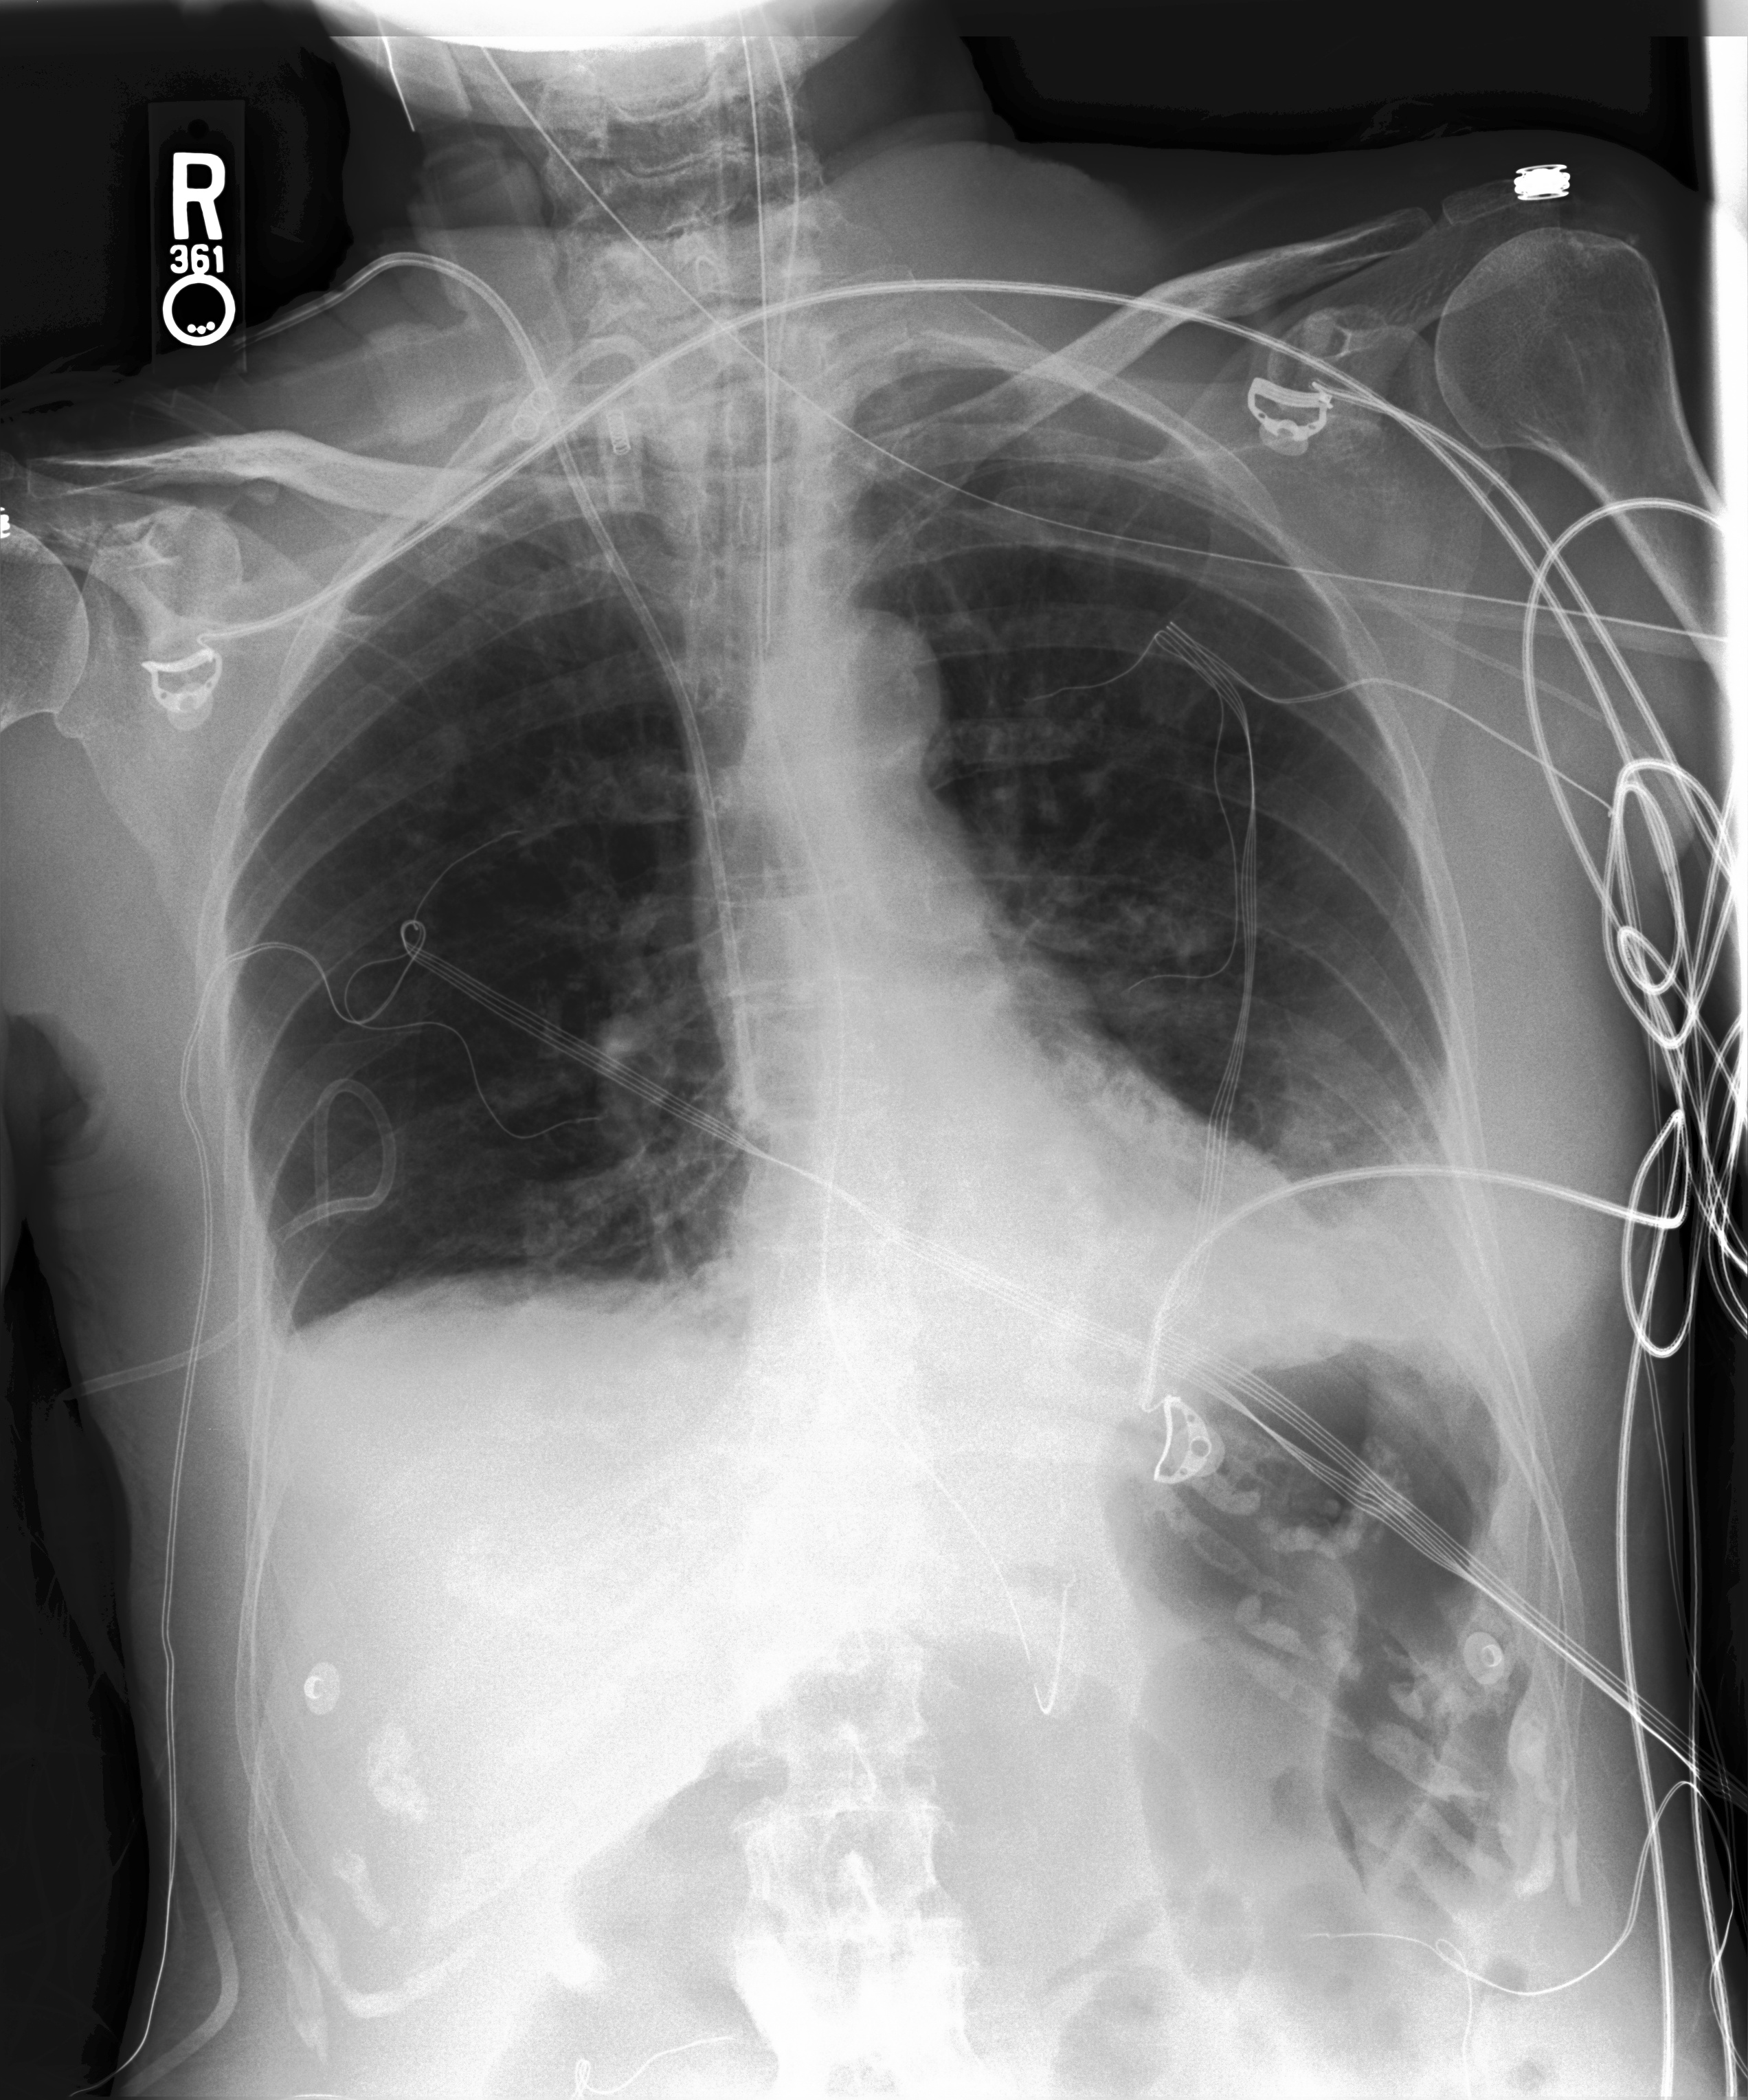

Chest X-Ray Ground Truth Our predictions

[Uncaptioned image] Compared to prior chest radiographs         through        . Previous mild pulmonary edema has improved, moderate cardiomegaly and mediastinal vascular engorgement have not. ET tube, right transjugular temporary pacer lead are in standard placements and an esophageal drainage tube passes into the stomach and out of view. Pleural effusions are presumed but not substantial. No pneumothorax. support devices present. no pneumothorax. pleural effusion present. lung opacity present. uncertain enlarged cardiomediastinum. no edema. atelectasis present. right internal jugular central line has its tip in distal superior vena cava. overall cardiac and mediastinal contours are likely stable given patient rotation on current study. lung volumes remain low with patchy opacities at both bases likely reflecting atelectasis. blunting of both costophrenic angles may reflect small effusions.